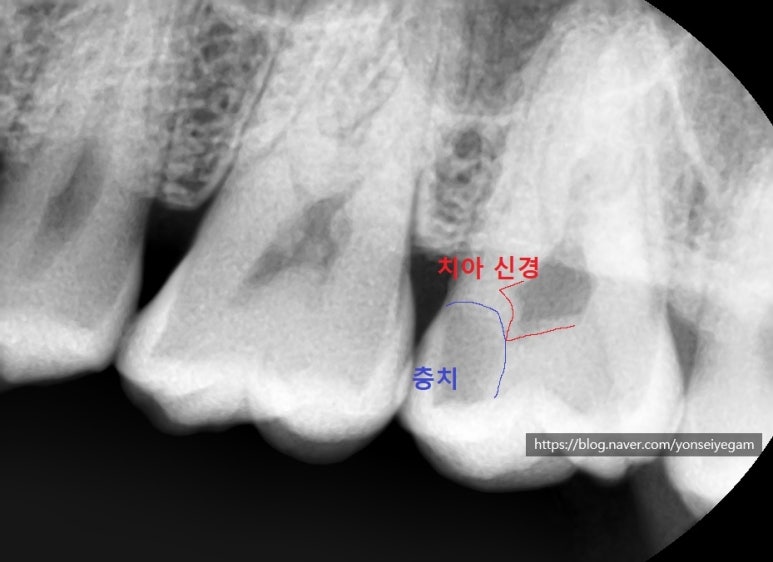

매우 치아 신경과 가깝게 충치가 있어서 그 치과의사분(원장님 친구분)도 당황하셨습니다. 치과의사라면 딱봐도 신경치료해야 될 상태였기 때문이죠. 아무 증상이 없었는데도 말이죠.

심지어 이렇게 치아 상에서는 그 부분이 크게 충치가 있는 것처럼 보이지 않는데도 말입니다. X-RAY의 중요성이지요. 이 분 같은 경우는 본인이 치과의사라서 저희 치과에서 정기적으로 엑스레이를 촬영하지 않았지만, 일반적인 환자분들 같은 경우는 정기검진과 정기적인 파노라마나 엑스레이 촬영이 필수입니다. 눈으로만 보는 것으로는 충치검진이 명확하지 않습니다.

이렇게 충치가 치아신경과 근접해 있어 신경치료가 필요한 것입니다.